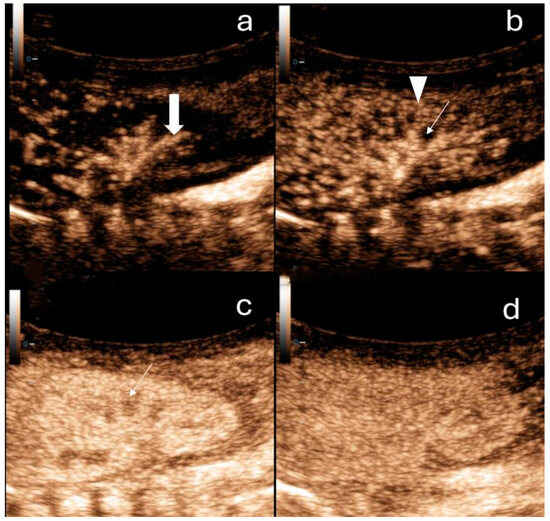

4. Sonographic Findings in AKI

- Kelahan, L.C.; Desser, T.S.; Troxell, M.L.; Kamaya, A. Ultrasound Assessment of Acute Kidney Injury. Ultrasound Q. 2019, 35, 173–180. [Google Scholar] [CrossRef]

- Yassa, N.A.; Peng, M.; Ralls, P.W. Perirenal Lucency (“kidney Sweat”): A New Sign of Renal Failure. Am. J. Roentgenol. 1999, 173, 1075–1077. [Google Scholar] [CrossRef] [PubMed]

- Granata, A.; Campo, I.; Lentini, P.; Pesce, F.; Gesualdo, L.; Basile, A.; Cantisani, V.; Zeiler, M.; Bertolotto, M. Role of Contrast-Enhanced Ultrasound (CEUS) in Native Kidney Pathology: Limits and Fields of Action. Diagnostics 2021, 11, 1058. [Google Scholar] [CrossRef]